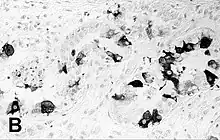

![]() | |

Encephalitis in the cerebral cortex of a harbor seal with PDV, stained with hematoxylin and eosin | |